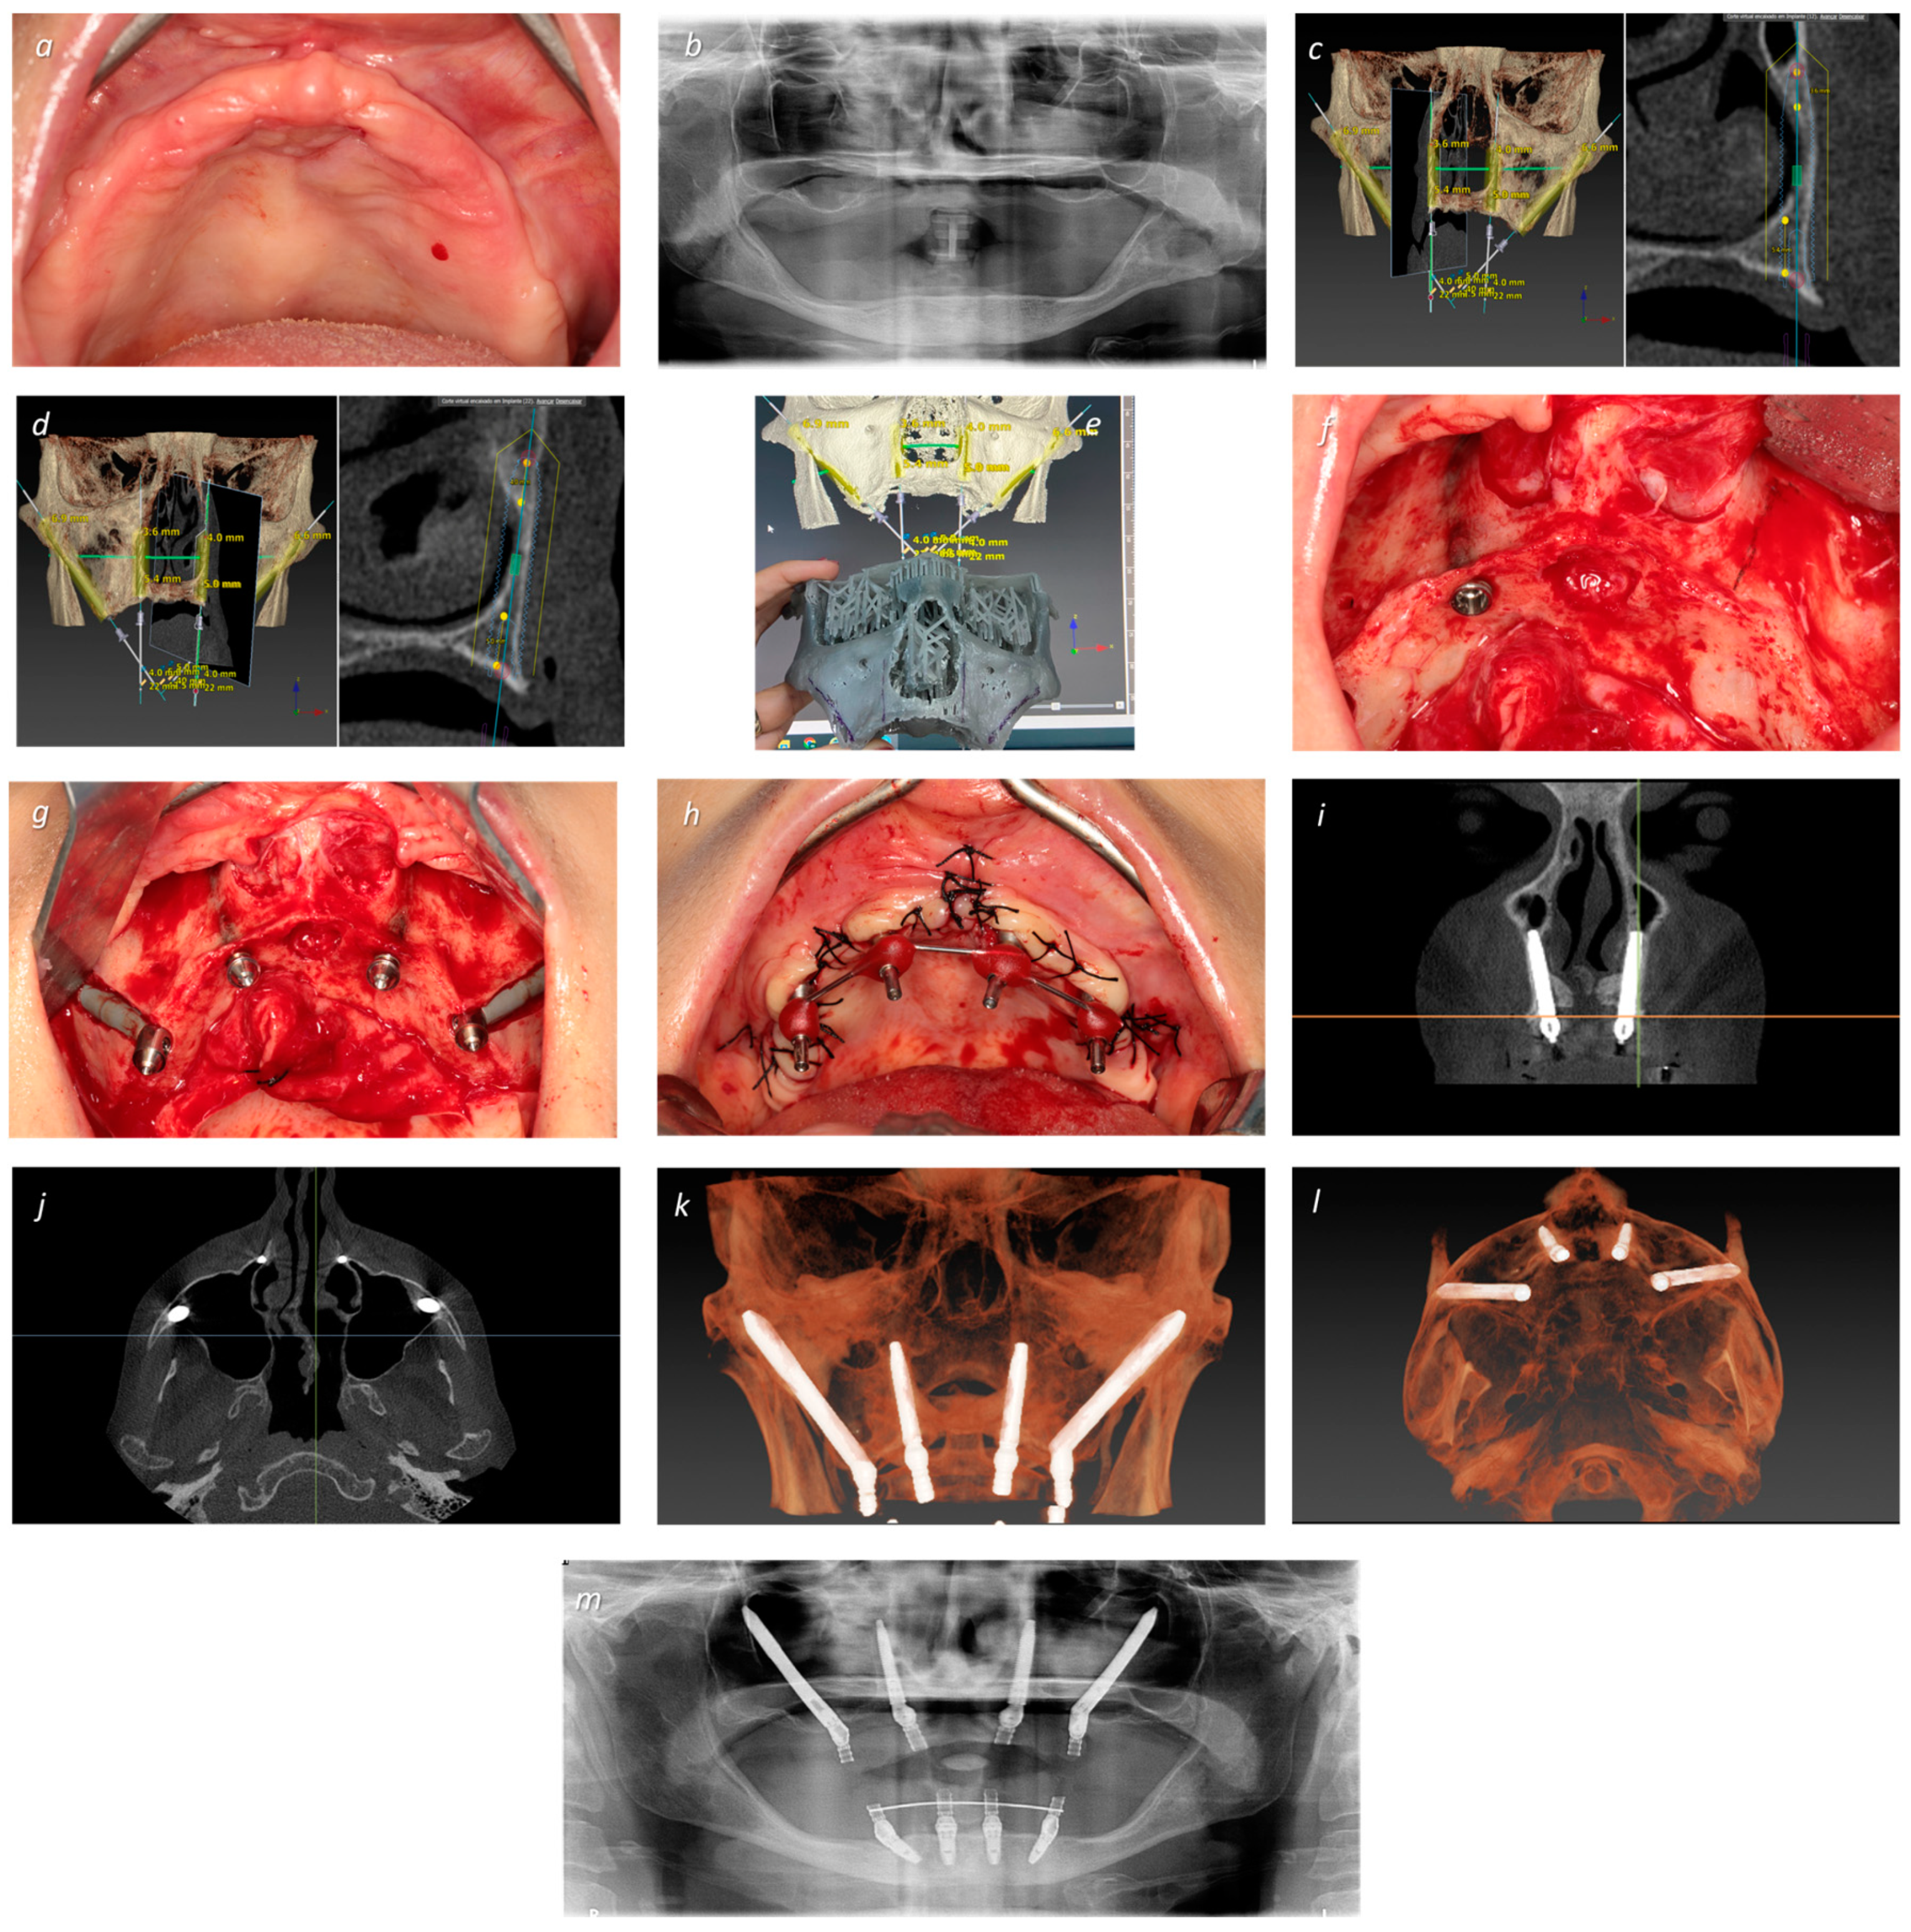

| 2 | EM 0° 5 × 40 | T 3.75 × 22.5 | T 3.75 × 22.5 | EM 0° 5 × 40 | 56 | F | 3 | I | NG | 50 |